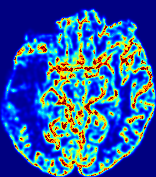

LesionRefer to captionRefer to captionRefer to captionRefer to captionRefer to captionRefer to caption𝐕rgbsubscript𝐕𝑟𝑔𝑏{\bf{V}}_{rgb}Refer to captionRefer to captionRefer to captionRefer to captionRefer to captionRefer to caption𝐕2subscriptnorm𝐕2{\|\bf{V}}\|_{2}Refer to captionRefer to captionRefer to captionRefer to captionRefer to captionRefer to captionRefer to caption3.53.53.52.82.82.82.12.12.11.41.41.40.70.70.70.00.00.0(mm/s)𝑚𝑚𝑠(mm/s)D𝐷DRefer to captionRefer to captionRefer to captionRefer to captionRefer to captionRefer to captionRefer to caption0.0200.0200.0200.0160.0160.0160.0120.0120.0120.0080.0080.0080.0040.0040.0040.0000.0000.000(mm2/s)𝑚superscript𝑚2𝑠(mm^{2}/s)Slice #1Slice #2Slice #3Slice #4Slice #5Slice #6

Figure 4: PIANO feature maps for another patient in the ISLES 2017 training set, where the lesion is located in the right hemisphere. Top row: segmented stroke lesion region (white) on different slices. The corresponding slices for the PIANO feature maps are shown in the following rows.

For a better insight into an estimated velocity field 𝐕𝐕{\bf{V}} and diffusion field 𝐃𝐃{\bf{D}}, we compute the following maps: (1) 𝐕rgbsubscript𝐕𝑟𝑔𝑏{\bf{V}}_{rgb}: Color-coded orientation map of 𝐕=(Vx,Vy,Vz)T𝐕superscriptsuperscript𝑉𝑥superscript𝑉𝑦superscript𝑉𝑧𝑇{\bf{V}}=(V^{x},V^{y},V^{z})^{T}, obtained by normalizing 𝐕𝐕{\bf{V}} to unit length and mapping its 3 components to red, green, blue respectively; (2) 𝐕2subscriptnorm𝐕2\|{\bf{V}}\|_{2}: 222 norm of 𝐕𝐕{\bf{V}}; (3) D𝐷D: scalar field in Eq. 5.

Fig. 3 and Fig. 4 show the PIANO feature maps estimated from two ISLES 2017 patients: all are highly consistent with the lesion in both cases. Details of the blood flow trajectories are revealed in 𝐕rgbsubscript𝐕𝑟𝑔𝑏{\bf{V}}_{rgb} by the ridged patterns and the sharp changes of colors in the unaffected (right) hemisphere, while the flat patterns appearing within the lesion provide little directional information about the velocity and indicate low velocity magnitudes. Velocity magnitudes are more directly visualized via 𝐕2subscriptnorm𝐕2\|{\bf{V}}\|_{2}, from which one can easily locate the lesion where 𝐕2subscriptnorm𝐕2\|{\bf{V}}\|_{2} is low. D𝐷D also indicates lower diffusion values in the lesion, though with less contrast potentially due to the fact that it captures the accumulated effect of CA diffusion at the voxel-level.